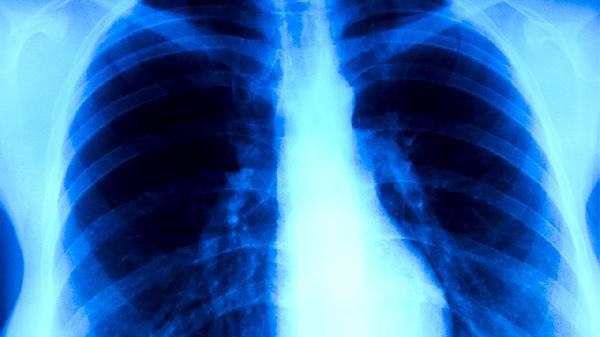

支原體肺炎恢復(fù)期咳白痰通常是呼吸道炎癥未完全消退的表現(xiàn),可能與氣道分泌物增多、黏膜修復(fù)過(guò)程有關(guān)。癥狀緩解需結(jié)合藥物治療與生活護(hù)理,主要有保證充足水分?jǐn)z入、保持空氣濕度、避免刺激性氣體、遵醫(yī)囑使用祛痰藥物、定期復(fù)查胸片等措施。

癥狀持續(xù)超過(guò)2周或痰量突然增多時(shí),需復(fù)查胸部X線或CT排除繼發(fā)感染。部分患者可能出現(xiàn)支氣管擴(kuò)張或肺不張等并發(fā)癥,早期發(fā)現(xiàn)可通過(guò)體位引流或支氣管鏡治療。兒童患者家長(zhǎng)應(yīng)記錄咳嗽頻率及痰液性狀變化。